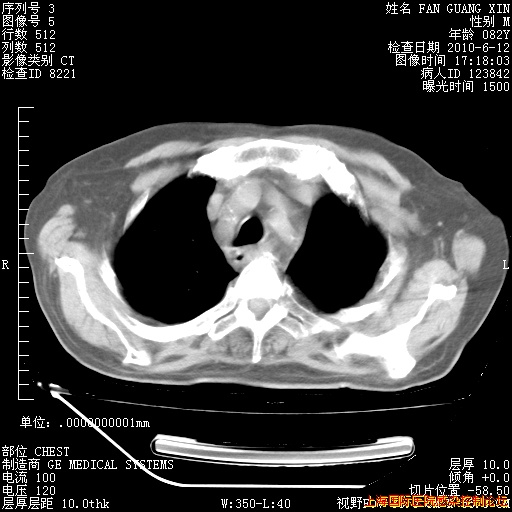

补发6月12日肺部CT肺窗

6月12日肺窗